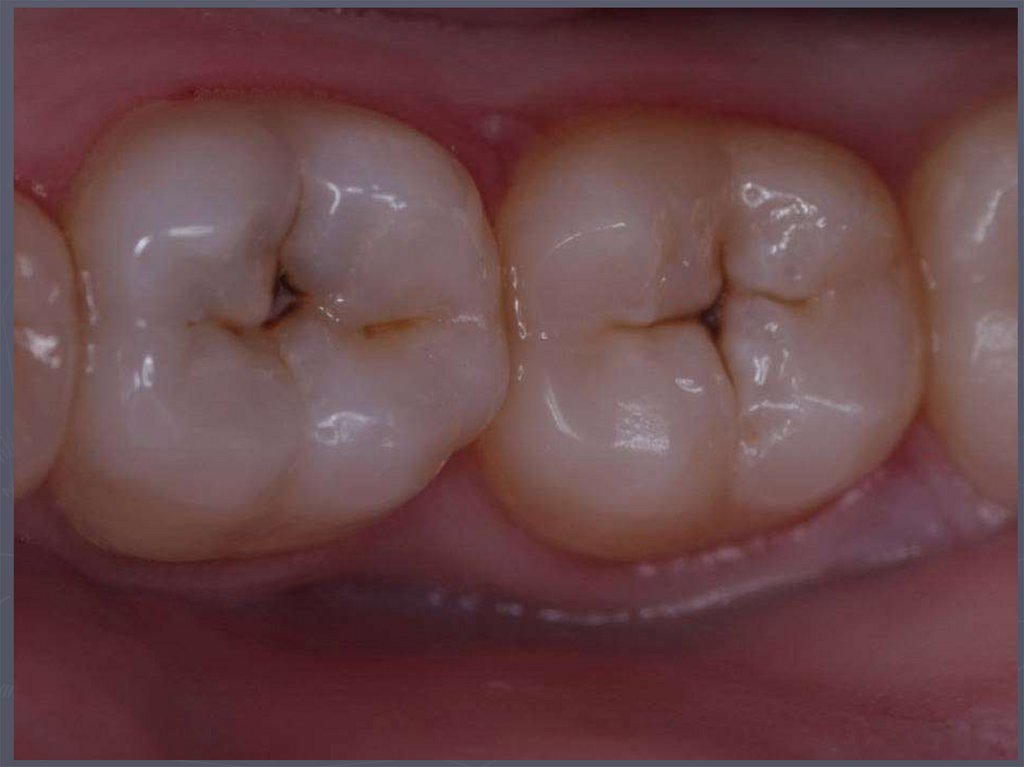

37. КЛИНИЧЕСКАЯ КАРТИНА СРЕДНЕГО КАРИЕСА при компенсированной форме:

► отмечается быстропроходящая боль от

химических, термических, иногда от

механических, раздражителей;

► края кариозной полости закругленные, ровные;

► эмаль плотная;

► дентин плотный, пигментированный;

► при зондировании болезненность определяется

по эмалево-дентинному соединению.

38. КЛИНИЧЕСКАЯ КАРТИНА СРЕДНЕГО КАРИЕСА при декомпенсированной форме:

► при локализации кариозной полости в фиссурах

определяется небольшое входное отверстие;

► при раскрытии обнаруживается кариозная

полость с податливым дентином;

► края кариозной полости нависают;

► эмаль тонкая, хрупкая;

► дентин светлый, влажный, размягченный, легко

удаляется экскаватором;

► зондирование болезненно по

эмалево-дентинному соединению.